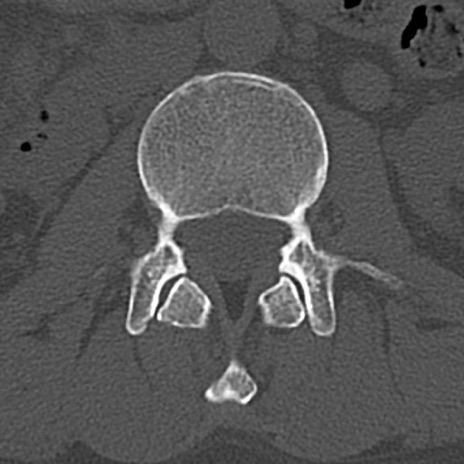

【整形】TIPS症例4 腰椎CT(横断像)

腰椎CT

横断像と矢状断像